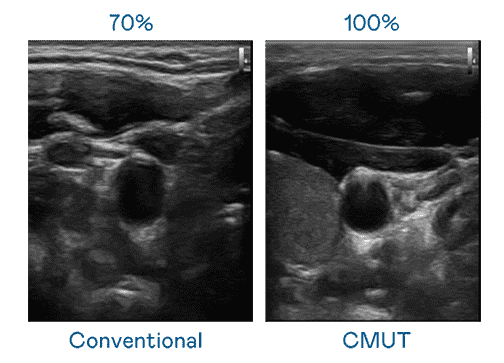

CMUT 技术是一种用电容式微机电元件来产生超音波讯号的技术。。。与传统 PZT 压电式技术相比,,,CMUT 频宽增加 30%,,更宽频的超音波讯号让影像解析度大幅提升,,是实现高影像品质医疗超音波扫描、、促进精准医疗发展的关键技术。。。。

大频宽带来超清晰影像

超音波影像的解析度高低,,,,首先取决于探头能发出的讯号频宽。。。尊龙集团 CMUT 可提供高清晰的超音波讯号,,,提供高频宽、、、高灵敏度、、、、影像纹理细节更高的超音波影像,,,协助医护人员缩短影像判读时间及利用精准的医疗影像进行诊断。。。。